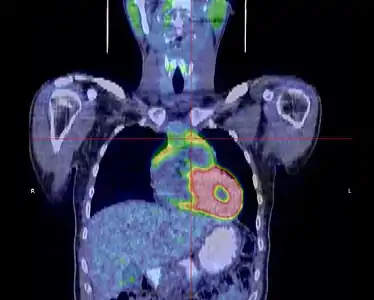

La place du TEP scanner dans le diagnostic des thymomes est encore débattue[31]. S'il existe bien une hyperfixation de la tumeur, son rôle dans le diagnostic de l'extension locorégionale reste à préciser[33].

- Thymome de type B1 en TEP scanner

Coupe transversale. Les trois clichés sont extraits du même examen.

Coupe frontale ; la tumeur est à l'intersection des lignes rouges.

Coupe sagittale ; la tumeur est à l'intersection des lignes rouges.